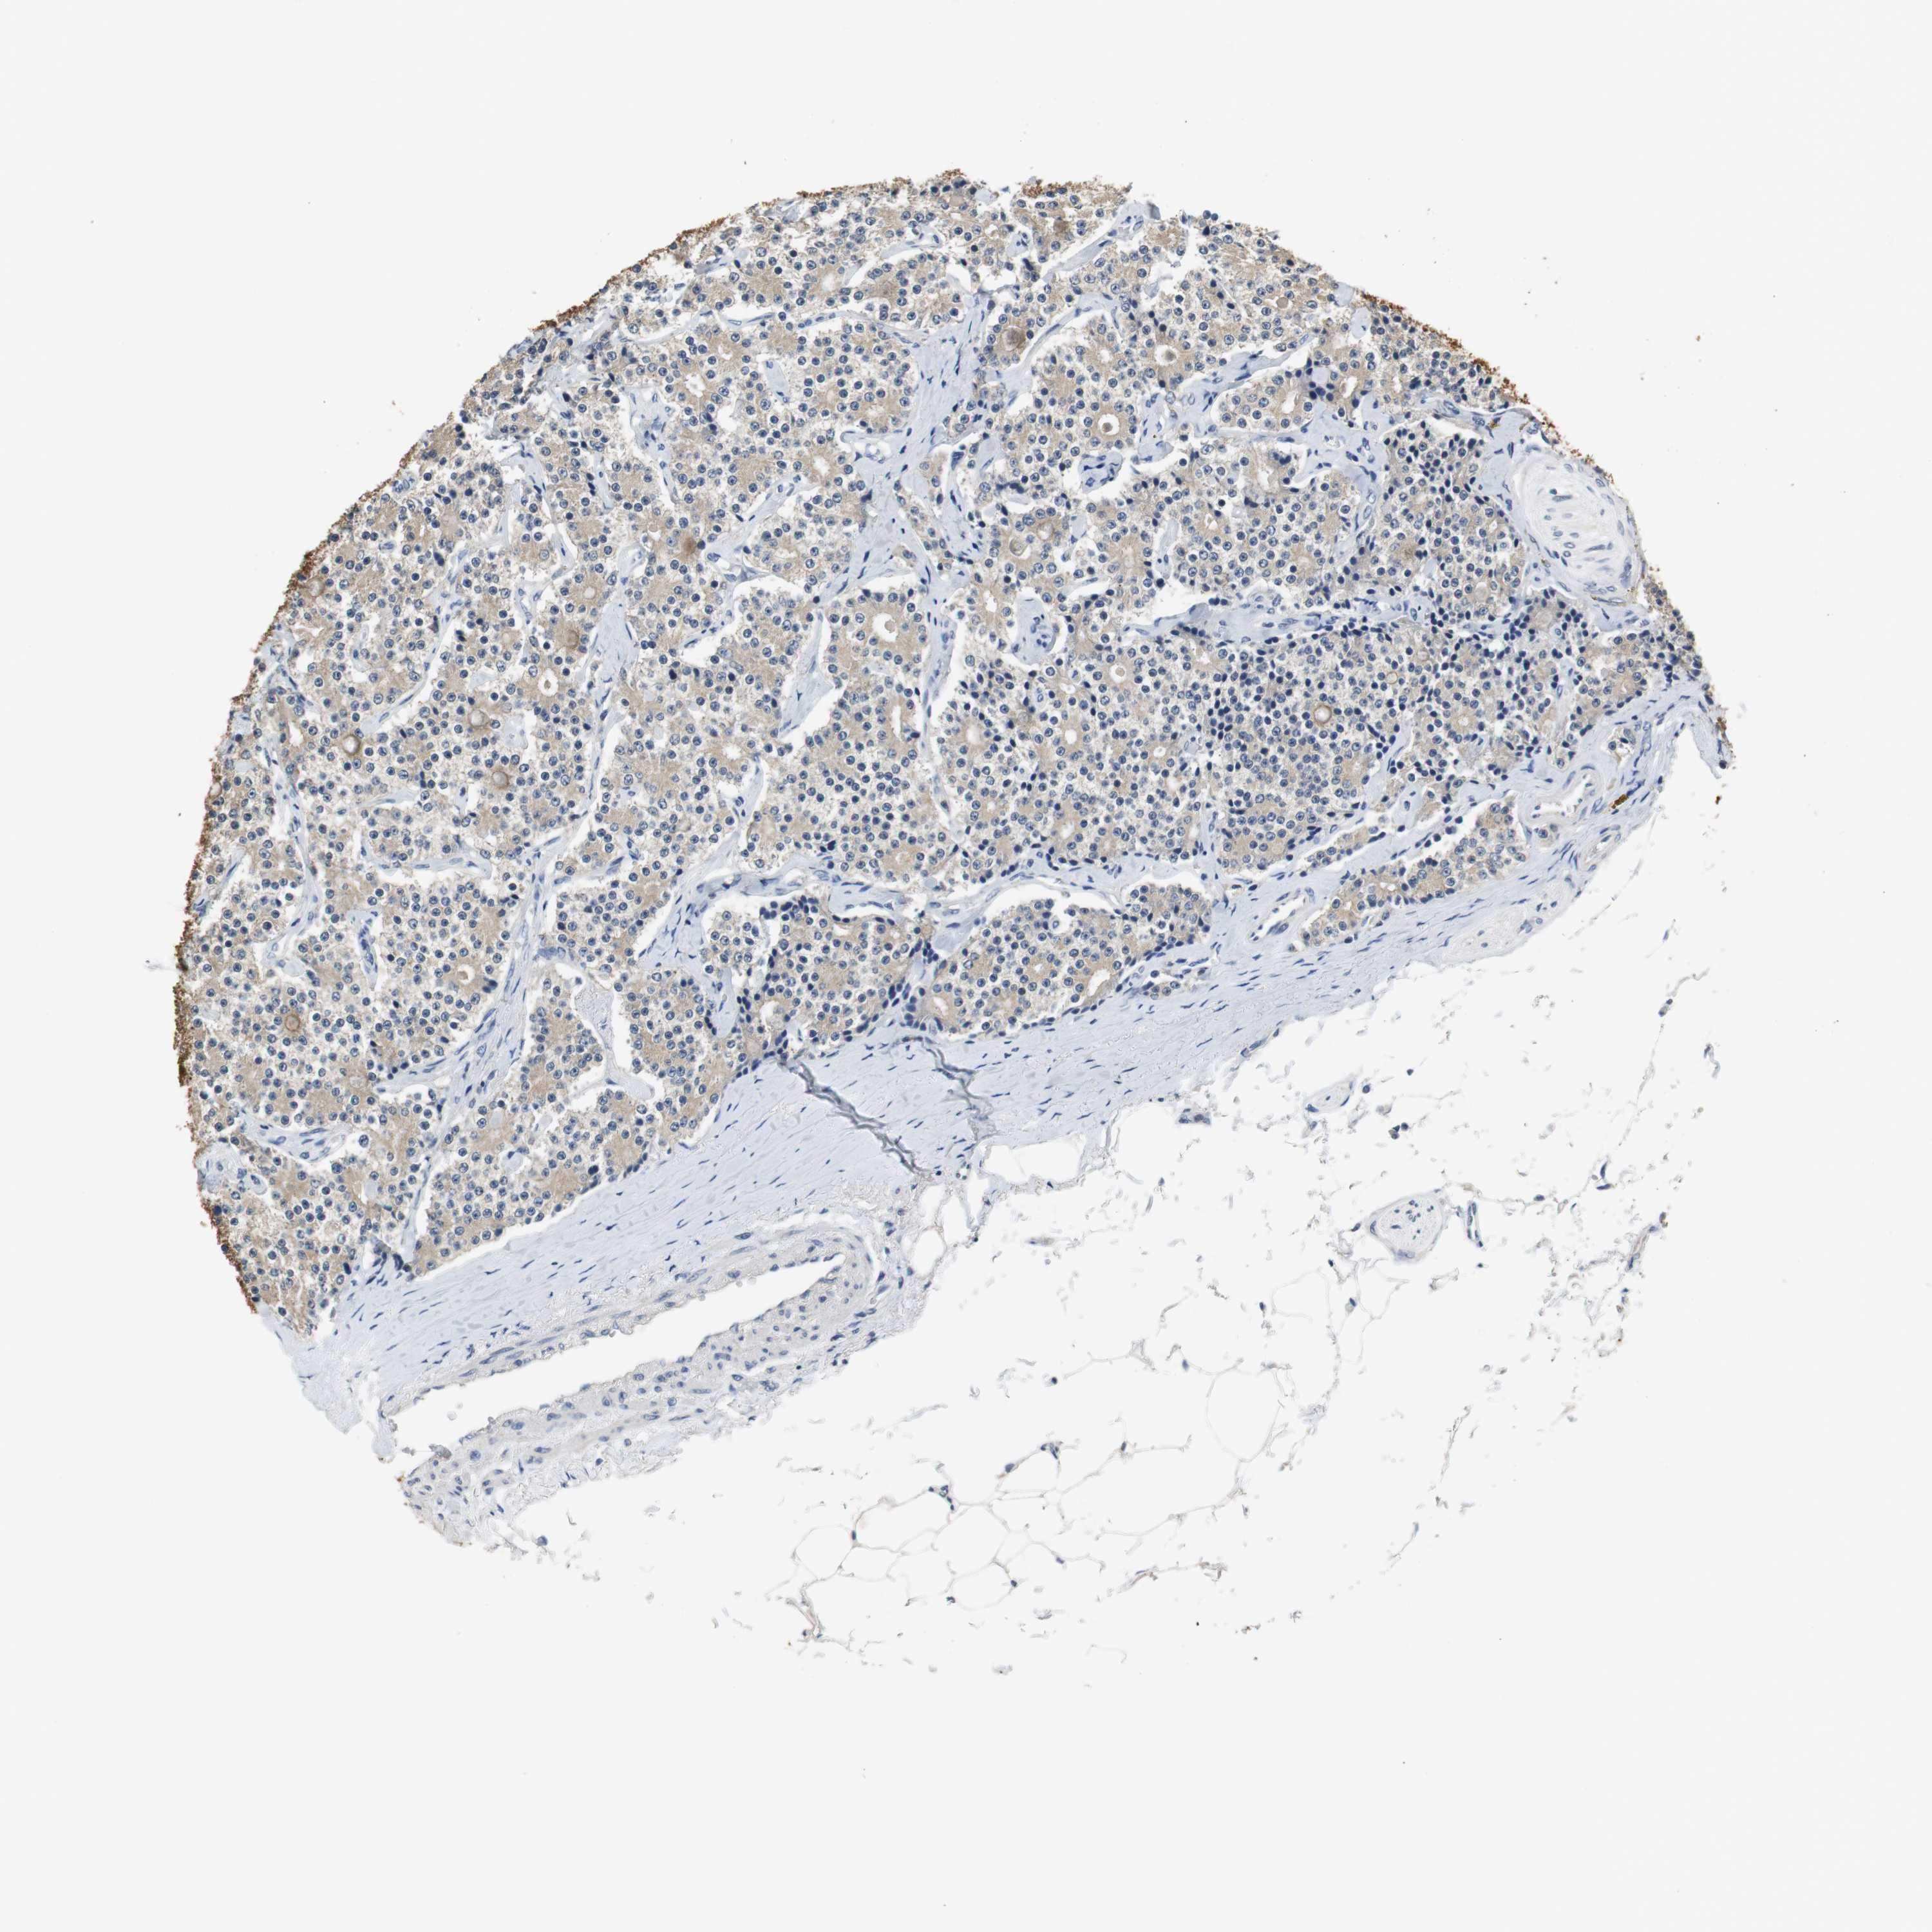

CARCINOID - Protein expressioni

A mouse-over function shows sample information and annotation data. Click on an image to view it in a full screen mode. Samples can be filtered based on level of antibody staining by selecting one or several of the following categories: high, medium, low and not detected. The assay and annotation is described here.

Antibody stainingi

Antibody staining in the annotated cell types in the current human tissue is reported as not detected, low, medium, or high, based on conventional immunohistochemistry profiling in selected tissues. This score is based on the combination of the staining intensity and fraction of stained cells.

Each image is clickable and will lead to virtual microscopy that enables deeper exploration of all samples and also displays staining intensity scores, fraction scores and subcellular localization as well as patient and tissue information for each sample.

Antibody HPA006277

Antibody HPA006507

Antibody CAB017027

Staining

High

Medium

Low

Not detected

Intensity

Strong

Moderate

Weak

Negative

Quantity

>75%

75%-25%

<25%

None

Location

Nuclear

Cytoplasmic/membranous

Cytoplasmic/membranous,nuclear

Carcinoid, malignant, NOS